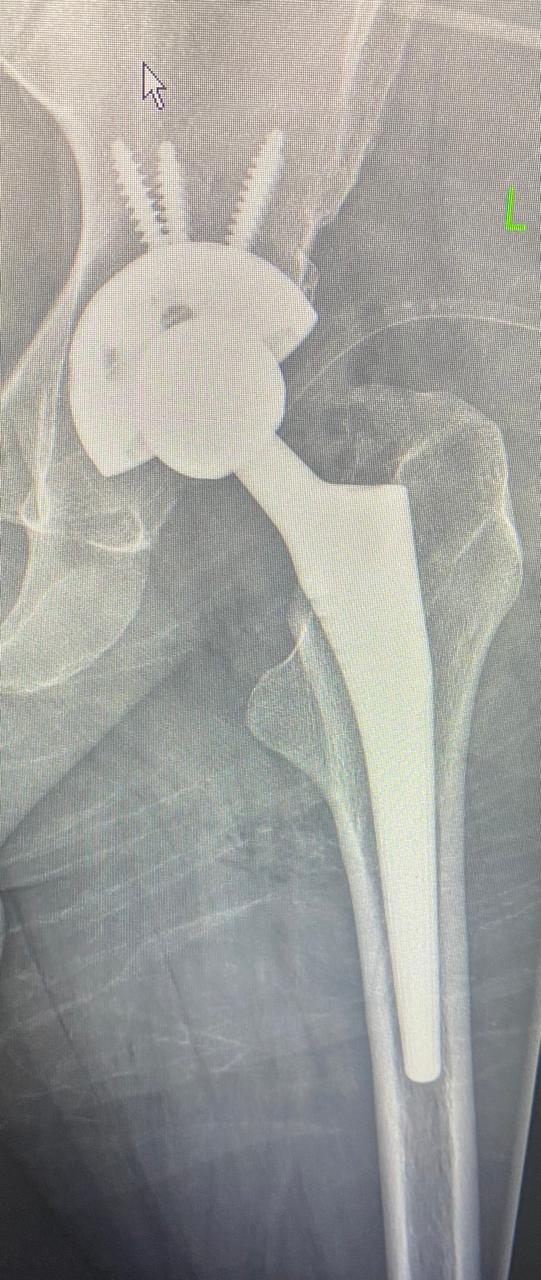

10

حسام الدين عبدالجليل

٣٠ عاما

يعاني من تاكل شديد منذ الطفولة في مفصل الحوض الأيسر.